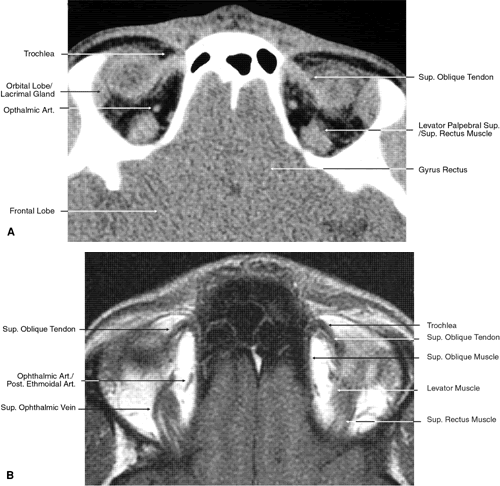

The globe is shown in Figure 12. The orbit and periorbital structures are shown in Figures 13 through 16, and the optic canal is shown in Figures 17 through 26. The cavernous sinus and optic chiasm are shown in Figures 27 and 28, and the posterior visual pathway and cranial nerves are shown in Figures 29 through 33.

Fig. 17. Coronal images through anterior orbit. A. Computed tomography scan. B. T1-weighted magnetic resonance imaging.

Fig. 18. Coronal images through midglobe. A. Computed tomography scan. B. T1-weighted magnetic resonance imaging.

The orbital roof is approximately triangular and is composed of the frontal bone anteriorly and the lesser wing of the sphenoid posteriorly. The roof is markedly concave, with the greatest degree of this concavity in the area of the equator of the globe (see Fig. 26). At the anterior and lateral portion of the orbital roof lies the lacrimal gland in the lacrimal fossa (see Figs. 18 and 23). This gland consists of a large orbital portion and a smaller palpebral portion. The orbital portion normally measures 20 × 12 × 5 mm, whereas the palpebral portion is about one third of this size.49 The supraorbital notch is at the junction of the nasal third and the lateral two thirds of the bony orbital margin (see Fig. 1). The trochlea of the superior oblique muscle is located 4 mm posterior to the orbital margin in the medial and anterior portion of the orbital roof (see Figs. 17, 24, and 25). Although usually a cartilaginous structure, it is occasionally partially or wholly ossified. It measures 4 × 6 mm and is firmly attached by connective tissue to the periosteum. The frontal bone portion of the orbital roof is extremely thin and like the orbital floor is subject to so-called blow-in fractures as well as to penetrating injury.50 The posterior portion of the roof is more substantial, measuring 3 mm thick. Except for the anterior portion of the orbit, the intracranial cavity lies directly superior to the orbital cavity (see Fig. 26). The levator muscle and the superior rectus muscle just inferior to it are present along the midportion of the orbital roof for all but its most anterior portion (see Fig. 26). The superior oblique muscle, after it changes direction at the trochlea, is present inferior to the anterior portion of the roof and inserts onto the globe inferior to the superior rectus muscle.

Anteriorly and medially, the frontal sinuses are superior to the orbit and lie between the two plates of the frontal bone. Occasionally, the ethmoid air cells are also found invading the orbital roof. The frontal sinus measures approximately 3 cm high,2.5 cm wide, and 2 cm deep. This is quite variable, and it is not unusual for one sinus to be considerably larger or smaller than the other or even completely absent. The two sinus cavities are separated by a bony septum that is usually deviated to one side. Medially the ethmoid air cells and nasal cavity lie below the frontal sinuses and are separated from them by a thin wall of bone. Superiorly and posteriorly the frontal sinuses are separated from the intracranial cavity and the frontal lobes by the thin frontal bone.

Immediately beneath the central portion of the orbital roof lies the frontal nerve, a branch of the ophthalmic division of the trigeminal nerve (see Fig. 18). Along with the trochlear nerve and lacrimal nerve, another branch of the ophthalmic division of the trigeminal nerve, it enters the orbit through the superior orbital fissure superior to the annular tendinous insertions of the extraocular muscles. The lacrimal nerve enters the orbit medial and superior to the superior orbital vein and travels laterally below the orbital roof and superior to the lateral rectus muscle to enter the lacrimal gland (see Fig. 24). The lacrimal artery arises from the ophthalmic artery lateral to the optic nerve and travels with the distal two thirds of the lacrimal nerve. The supraorbital and supratrochlear arteries branch from the ophthalmic artery superior to the optic nerve, passing medially to the superior rectus and levator muscles to accompany the supraorbital and supratrochlear nerves, the two branches of the frontal nerve, as they pass above the levator muscle. The supraorbital vein and artery accompany the nerve along the anterior two thirds of its course before exiting with it at the supraorbital notch. The other branch of the frontal nerve, the supratrochlear nerve, travels medially after separating from the frontal nerve at approximately the junction of the posterior one third and anterior two thirds of the orbit. The trochlear nerve diverges from the frontal nerve in the posterior orbit, passing medially below the orbital roof and above the levator and superior rectus muscles to enter the superior aspect of the posterior half of the superior oblique muscle.